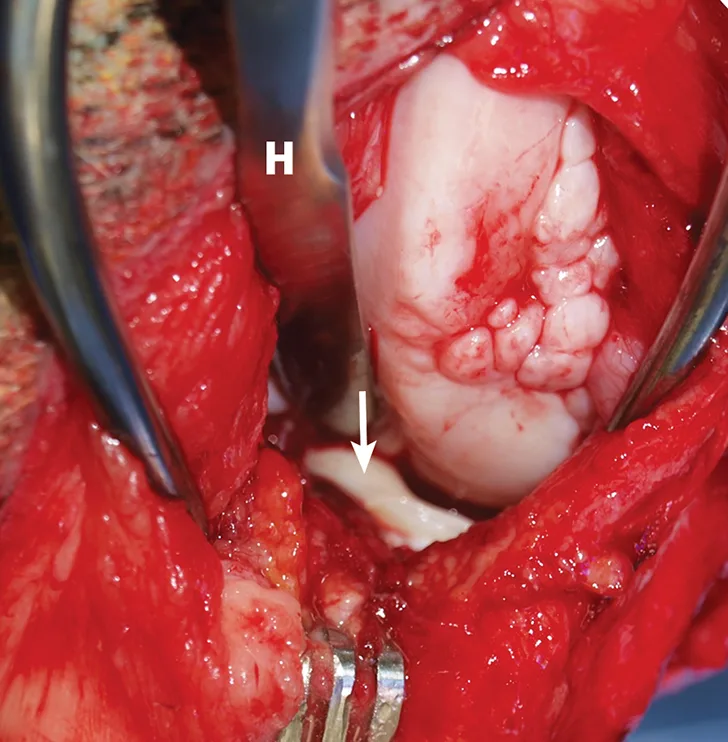

Intraoperative image with close-up of torn medial meniscus.

FIGURE 3

Intraoperative image demonstrating identification of medial meniscal tears by craniomedial arthrotomy in the dog in Figure 2. A Hohmann retractor (H) has been placed to allow inspection of the caudal joint space. The caudal pole of the medial meniscus has sustained a bucket handle tear and is flipped cranially (arrow).

Surgical exploration of the stifle joint is typically used to identify tears in the meniscus. The most accurate method for diagnosing a meniscal tear is joint evaluation by arthroscopy or arthrotomy, combining visual evaluation and careful palpation of the meniscus with a meniscal probe.41 A stifle distractor or Hohmann retractor may be necessary to facilitate adequate access to inspect the caudal portions of the joint (Figure 3). Both menisci should be carefully evaluated to identify all damaged regions.41 Failure to identify and treat meniscal tears is a common cause of poor function following surgery for CCL rupture.24,30,41,42